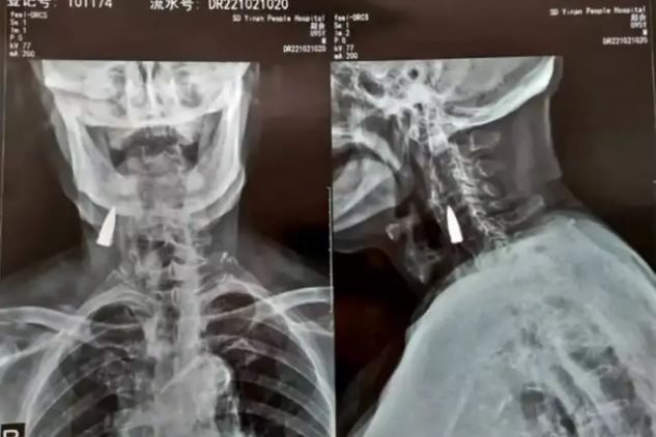

La radiografía del anciano chino de 95 años con la bala en su cuello

Zhao He, veterano de guerra que recientemente sufrió una caída aparatosa desde el balcón de su casa Shandong (China). Tras acudir al médico para hacerse un chequeo de los daños, con una radiografía incluida, el veterano de guerra descubrió para su sorpresa, que llevaba viviendo 77 años con una bala incrustada en su cuello.

Y es que, en un principio, la caída no le causó dolores, pero con el paso de los días comenzó a sentir una leve molestia en el cuello. Su hijo fue quien finalmente, lo llevó al médico para que le chequearan con una radiografía, que les desveló que tenía un cuerpo extraño que más tarde identificaron como una bala vieja.

Al determinar que la bala se encuentra cerca de algunos vasos sanguíneos importantes y que hasta el momento no había ocasionado ningún problema, los médicos comunicaron a Zhao He que lo más adecuado sería dejarla dentro. "He estado sano siempre, así que no hay razón para cambiar las cosas ahora", aseguró el anciano.